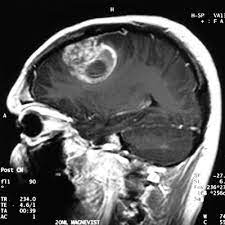

Астроцитома второй степени злокачественности называется фибриллярной или диффузной. Это глиальная опухоль, возникающая в любом возрасте, в том числе у детей.

Онкологическая патология, для которой характерно развитие опухолевого очага в области спинного или головного мозга появляется из таких клеток как астроциты, содержащиеся в нейроглии. Вторая стадия роста опухоли еще считается низкозлокачественной, но уже способной к малигнизации. Опухоль имеет выраженные границы, отделяющие ее от здоровых тканей, и медленно увеличивается в размерах.

Это позволяет обнаружить точную локализацию диффузной астроцитомы, ее величину и интенсивность развития, оценить состояние окружающих тканей. Для определения вида опухоли и степени злокачественности проводится биопсия с изучением взятого образца. В лечении применяется комплексный подход, направленный на удаление опухолевого очага и возможных, распространившихся метастаз.